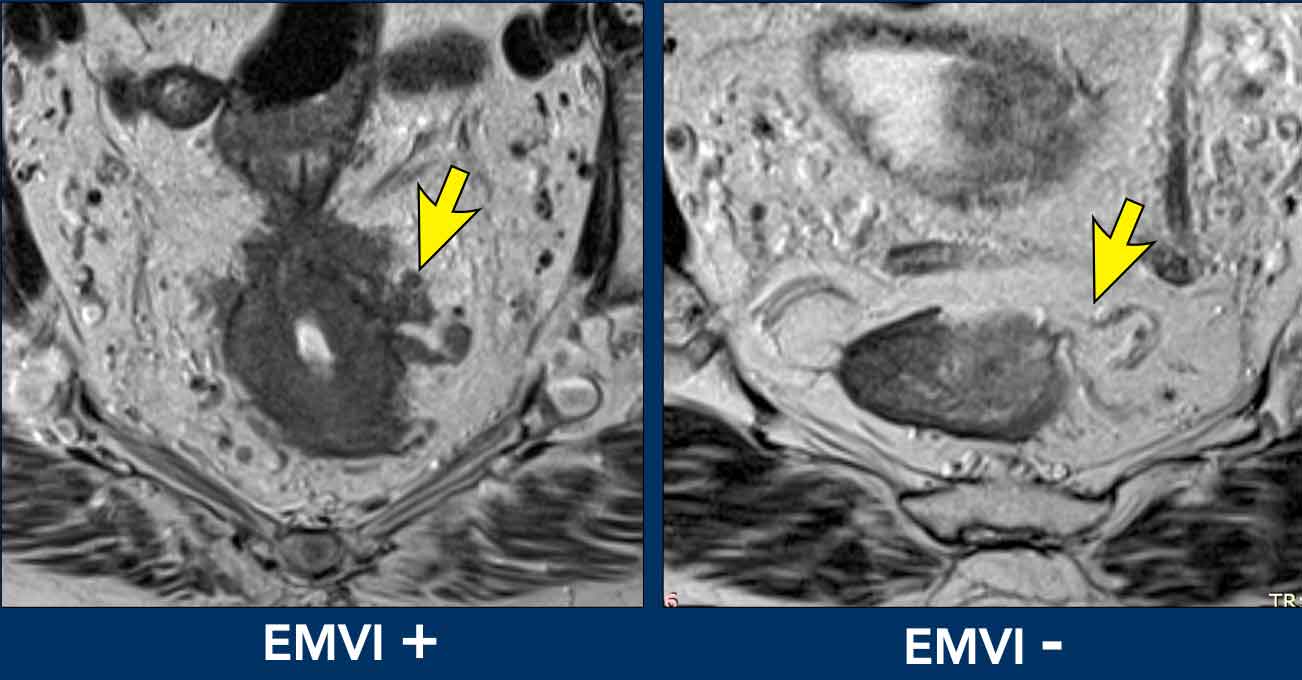

EMVI is suspected if we see tumor-signal extending into an adjacent vessel, when the vessel is expanded by tumor, or if the tumor disrupts the vessel borders (illustration).

EMVI can be graded as follows [ref]:

• 0 = no nodular extension beyond the muscularis propria and no vessels adjacent to areas of tumor extension

• 1 = Minimal nodular extension or stranding, not in the vicinity of vascular structures

• 2 = stranding in the vicinity of extramural vessels, with vessel of normal caliber and no tumor signal extending into the vessels

• 3 = tumor signal extending into vessels, with normal or slightly expanded vessel contour

• 4 = tumor signal extending into vessels with clear disruption of vessel contour and/or nodular expansion of the vessels

Grades 3 and 4 should be reported as EMVI+ disease.

Grades 0-2 as EMVI-.

Image comparison

• Left (EMVI+): Tumor signal clearly extends into adjacent vessels, disrupting their contours.

• Right (EMVI-): Vessels maintain smooth contours with no tumor signal present.